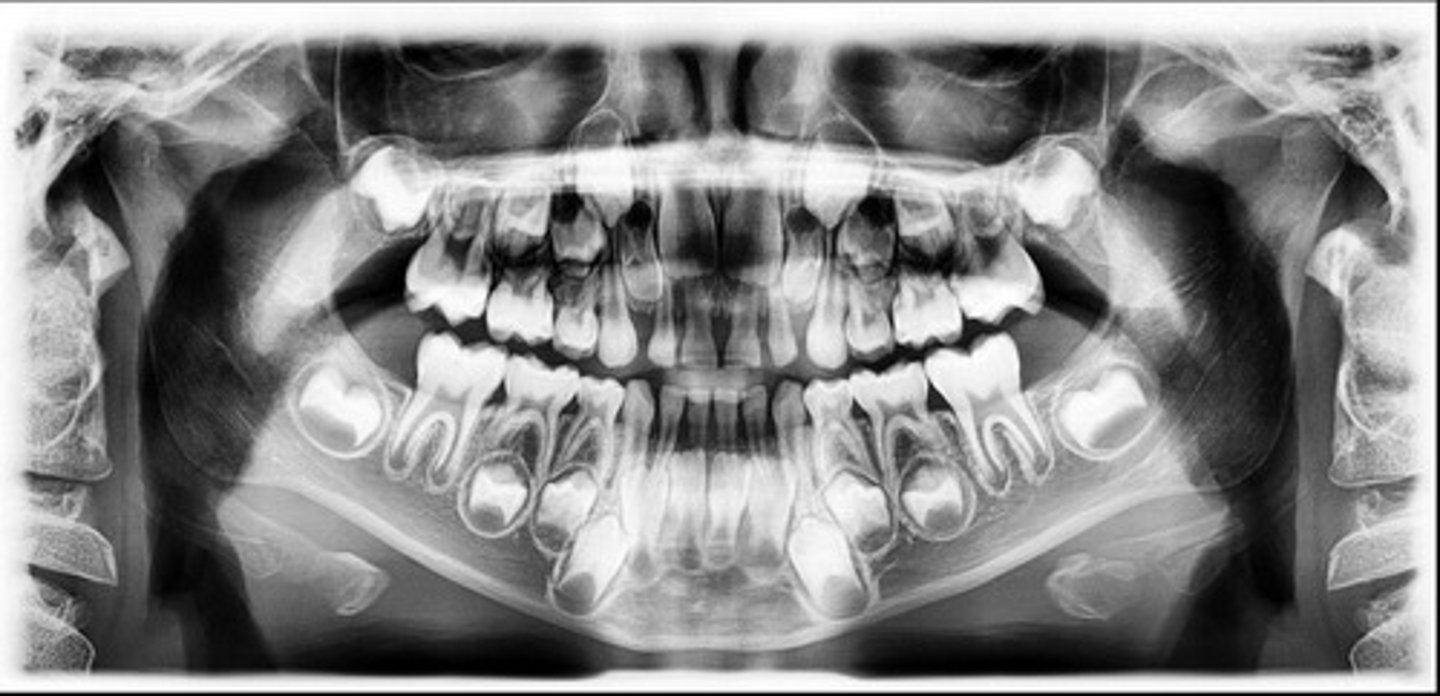

8 years old

How old do you think this child is?

<p>How old do you think this child is?</p>